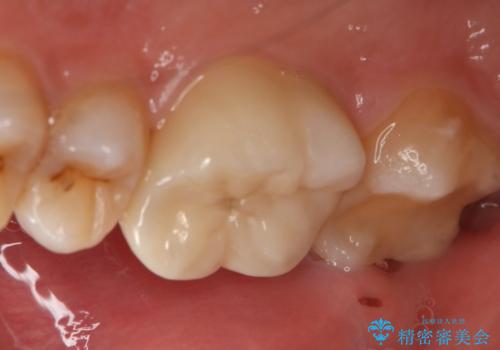

- 右上下6番の銀歯のやり変えを希望された患者様です。

切削量・形態を考慮し、上はセラミッククラウン、下はセラミックインレーでの治療を選択しました。

上はう蝕が歯頚部まで達していたのでクラウンでの治療を選択しました。

銀歯直下もう蝕が進行していたので全て除去した上でCRにて裏層しています。

下はクラウンほど切削量が多くないと判断し、インレーでの治療を選択しました。